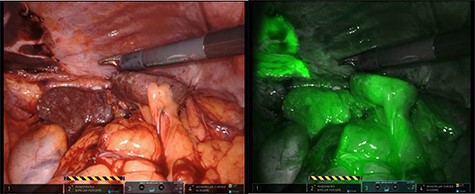

After mobilization of the left liver lobe, visualization of the hiatus was achieved. A two silk suture was placed through the avascular hepatogastric ligament and outside the patient’s anterior abdomen with an extracorporeal knot in order to assure atraumatic elevation-retraction of the liver. Space was created in the surgical field due to the absence of a retracting surgical instrument within the abdominal cavity. The hernia’s sac was then dissected with use of energy device and bipolar cautery with minimal traumatic tissue handling; the herniated stomach, transverse and left colon, omentum and finally spleen were dissected free (Fig. 2). Due to the atypical clinical symptomatology as well as increased PLT, the suspicion of chronic ischemia of the herniated organs was raised. ICG was administered to assess the patency of blood supply in the herniated organs and specially to the spleen; blood supply was excellent and as a result, no further resections were needed (Fig. 3). An 8- × 4-cm posterolateral diaphragmatic defect was revealed; the defect was repaired with the use of ProGrip mesh and was supported by a continuous V-loc suture for fixation. The patient resuscitated from anesthesia in great condition and returned to the ward, with an uneventful course. A post-operative upper GI fluoroscopy was conducted at the second post-operative day (POD), and oral diet was commenced (Fig. 4).

The use of intraoperative ICG and the use of Firefly camera to assess blood supply and viability of the spleen.

The use of ICG while utilizing the Firefly camera of the DaVinci Xi Robotic System is another innovation used in this case. It is the only case reported of leftside Bochdalek hernia in international literature, which utilizes such contrast media intraoperatively. Assessment of blood supply with a harmless substance at the time of operation is an undeniable weapon in the surgeon’s arsenal in order to provide the patient with the optimal treatment without inadvertently assuming false blood supply of the herniated organs. The phenomenon of ischemia in such hernias has been reported and further anatomical dissections were required [10, 14, 15]. Macroscopic alteration of blood supply could be absent at time of operation, so intraoperative ICG green application readily evaluates such cases.